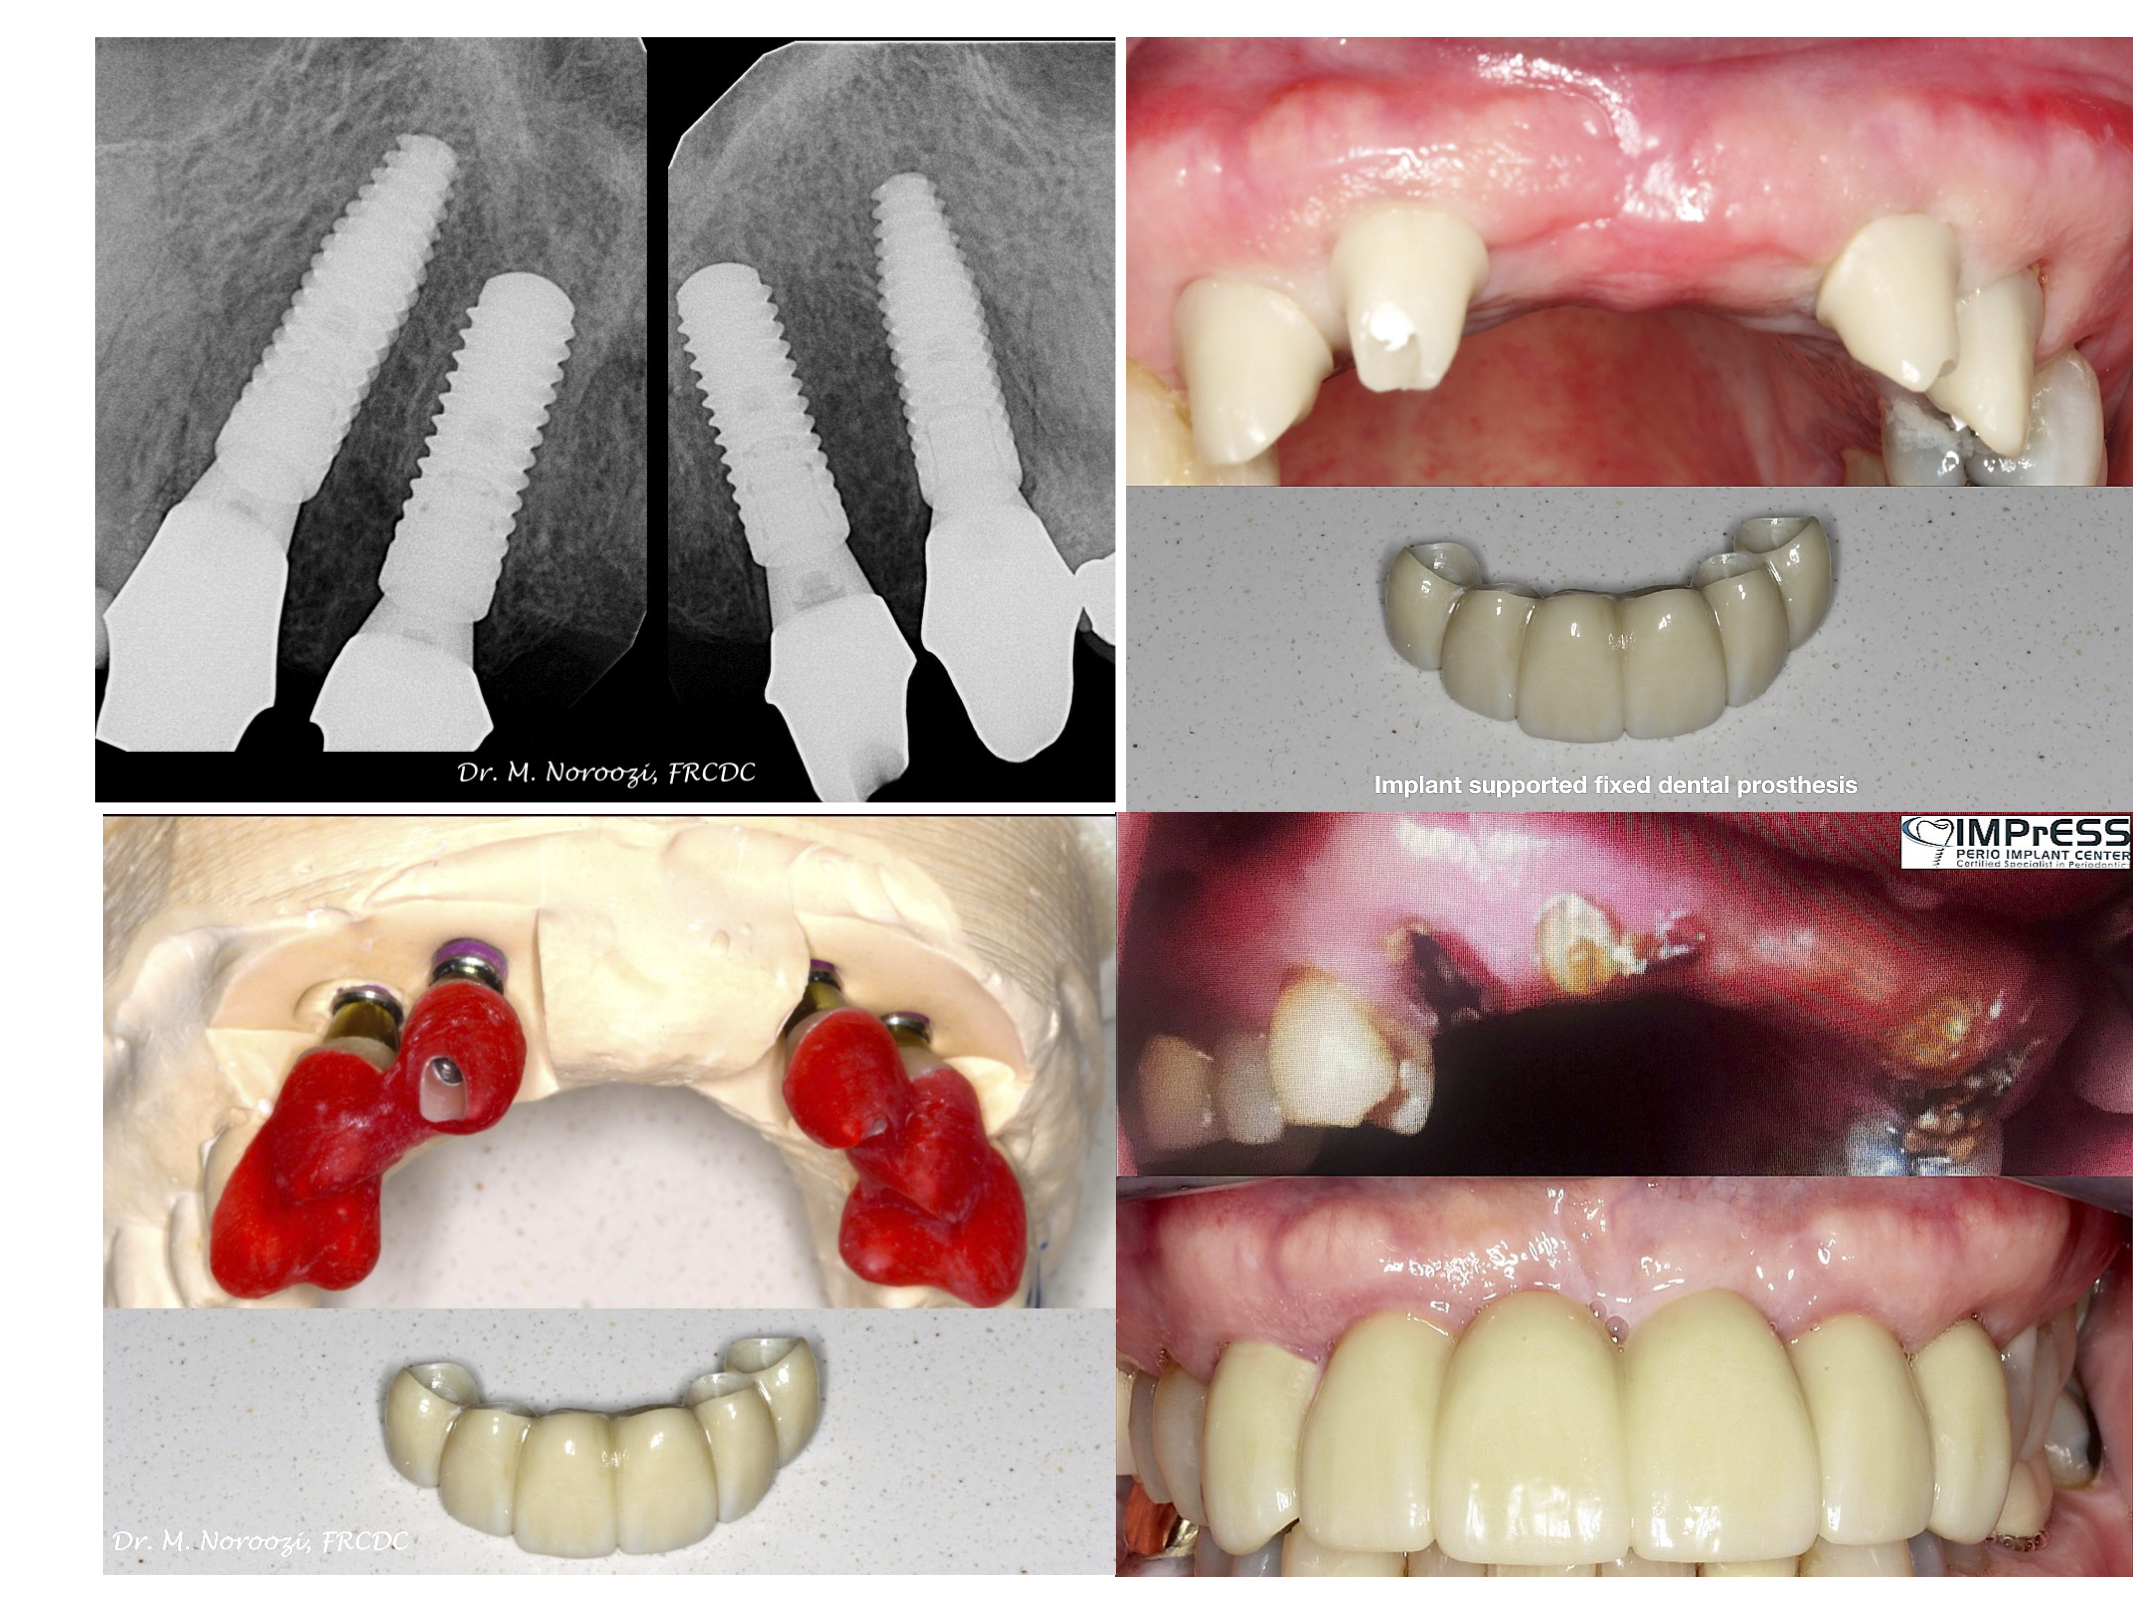

Before & Afters of Dental Implant Patients

Complete Dental Implant Cases Gallery

• When replacing several teeth or all of your teeth, a fixed bridge is anchored to your dental implants. A bridge is a dental restoration that replaces one or more missing teeth by spanning an area that has no teeth. The bridge is held firmly in place by dental implants on each side of the missing tooth or teeth.

General Disclaimer: The results in the photographs are examples only and do not imply any certainty of the result of a procedure, and all outcomes are subject to the circumstances of the individual patient.